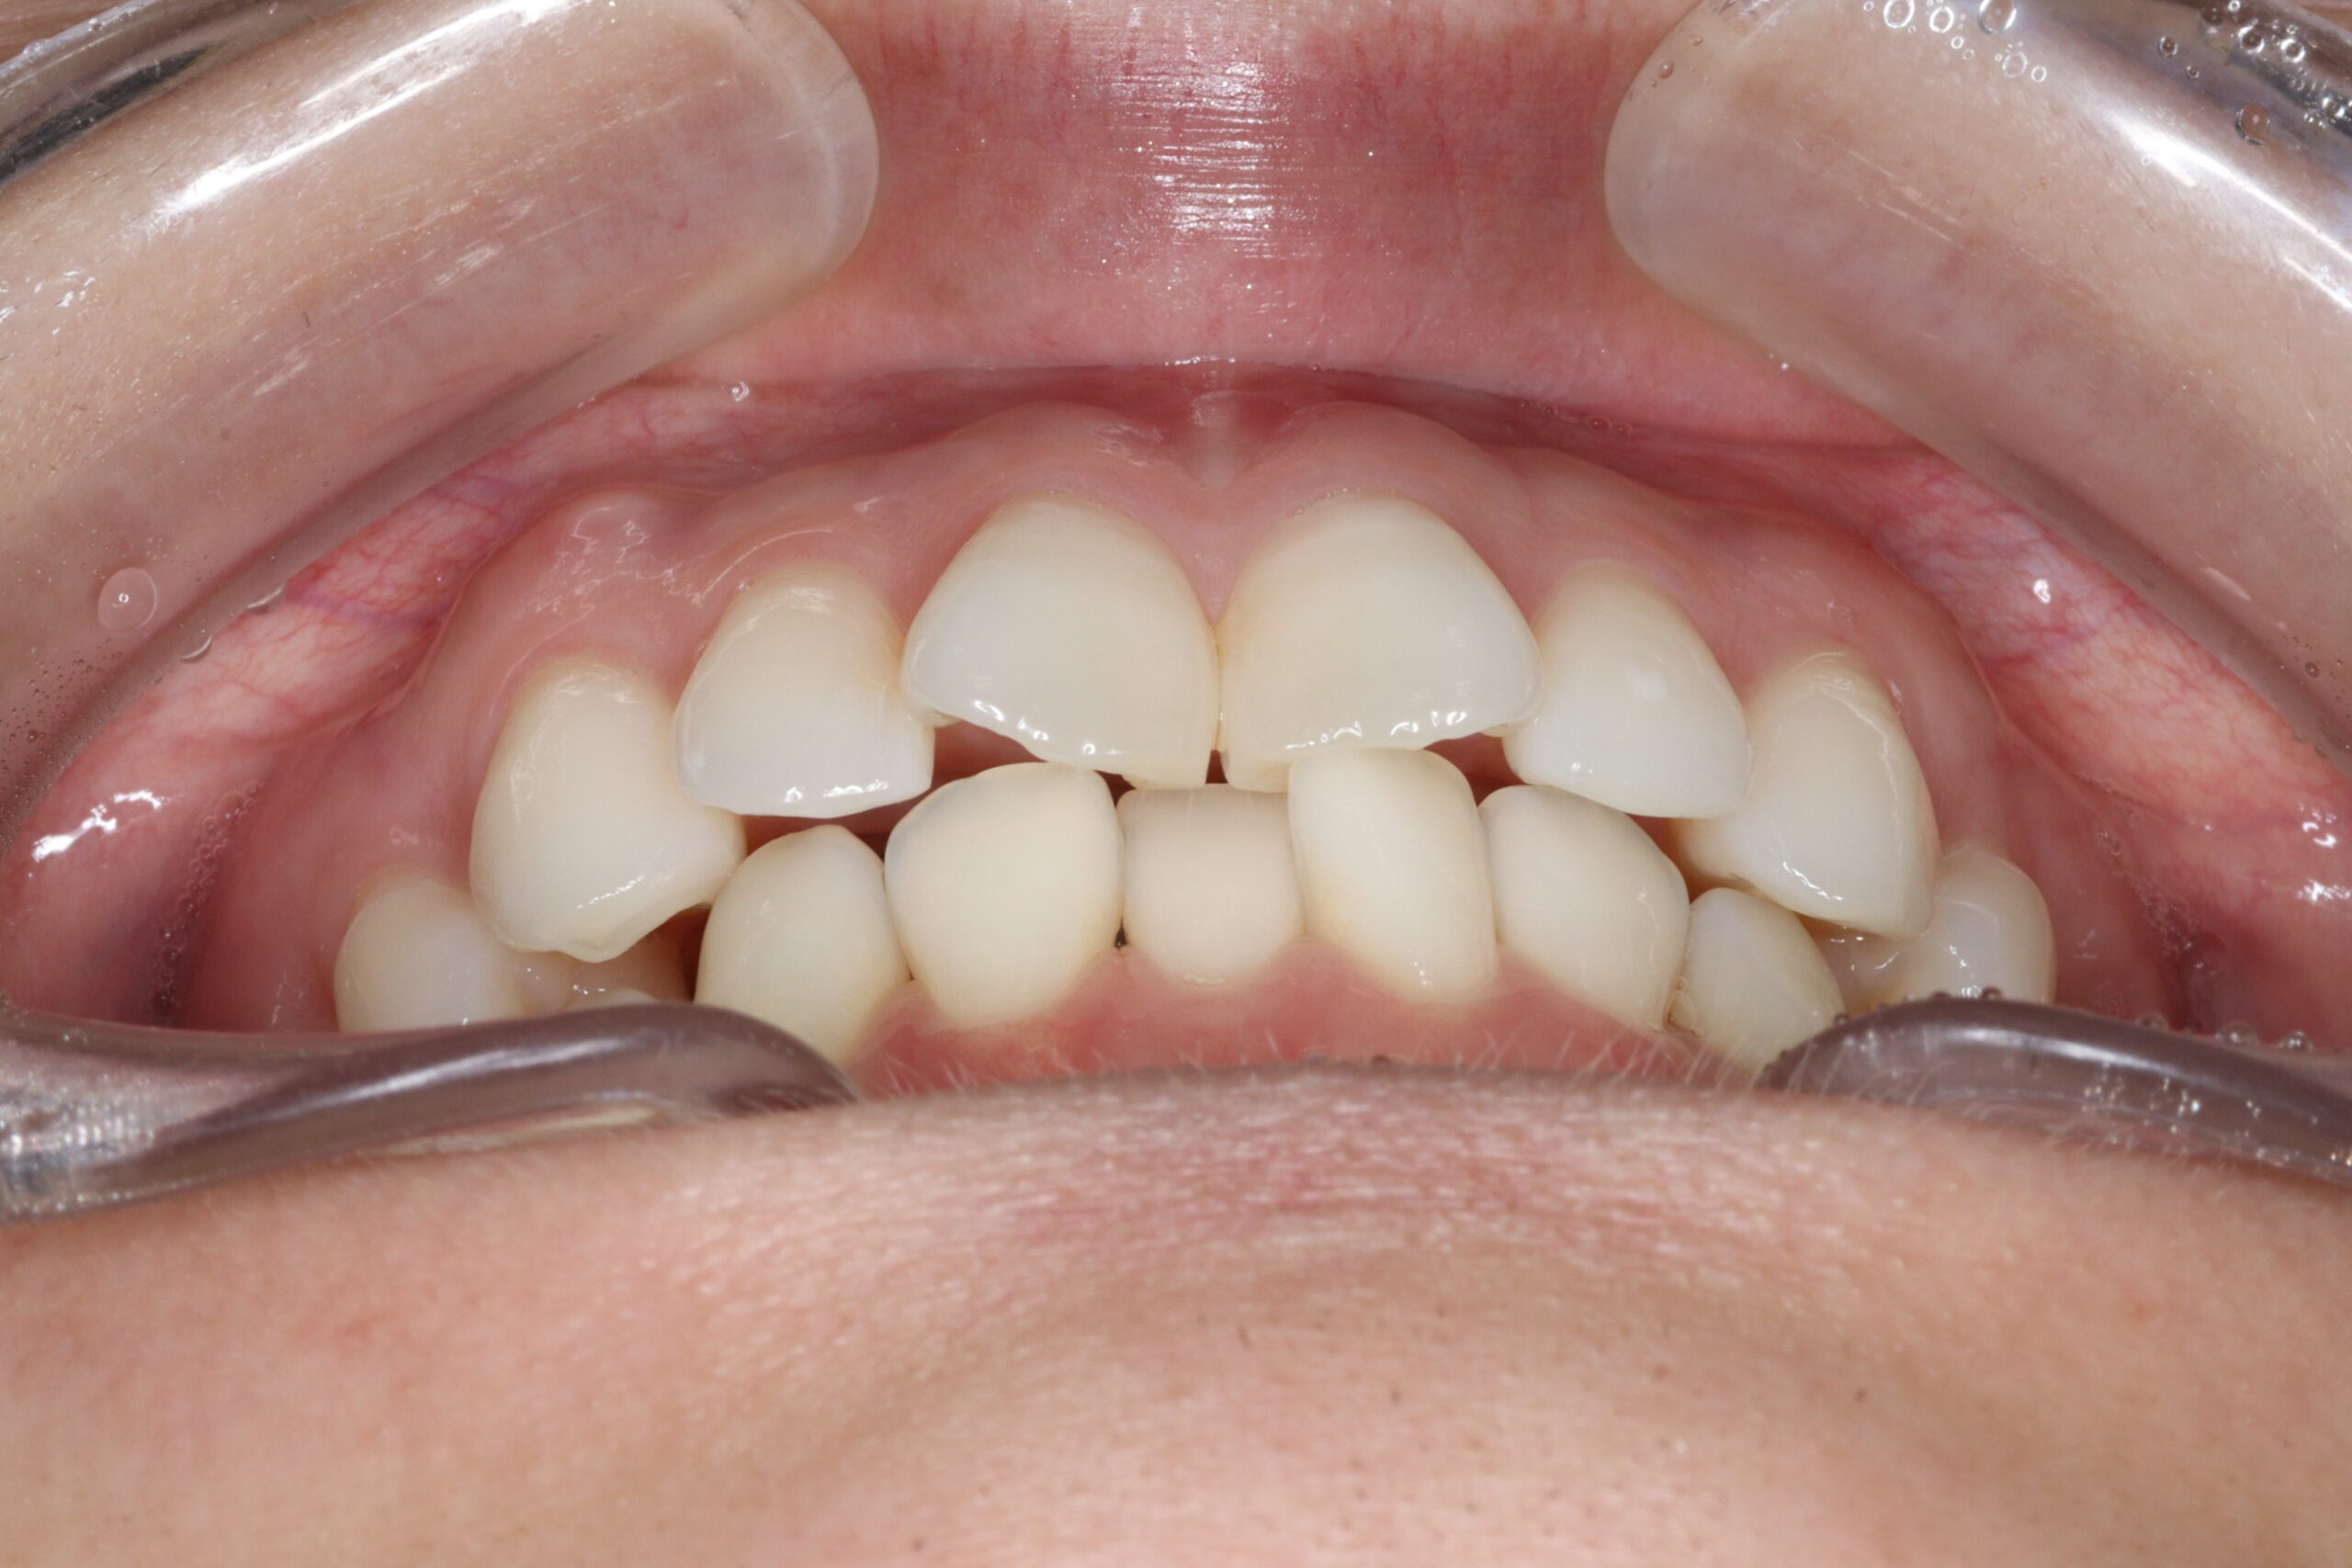

矯正術前:正面

矯正術後:正面

| 主訴 | 上下の前歯のがたつきと捻じれが気になる。 |

| 治療内容 | 上下の前歯のがたつきと捻じれを気にされており、矯正検査後叢生Ⅰ級と診断いたしました。 |